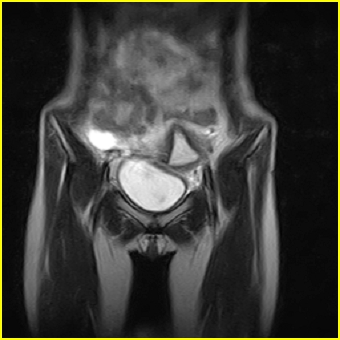

女、15岁、下腹疼痛2天,排尿困难1天。查体:处女膜闭锁,距处女膜约4至5cm处扪及一约5cm直径的圆形包块,张力较高,触痛明显、欠活动。b超提示子宫增大伴宫内增强回声团。

影像意见:子宫直肠陷凹积血。

更正影像意见:阴道积血。

处女膜闭锁,阴道积血

处女膜闭锁,阴道积血,子宫积血.

先天性处女膜闭锁,伴阴道积血,不除外先天性阴道粘液囊肿形成。

阴道积血,子宫积血.

子宫及阴道积血。

处女膜闭锁,伴子宫及阴道积血.